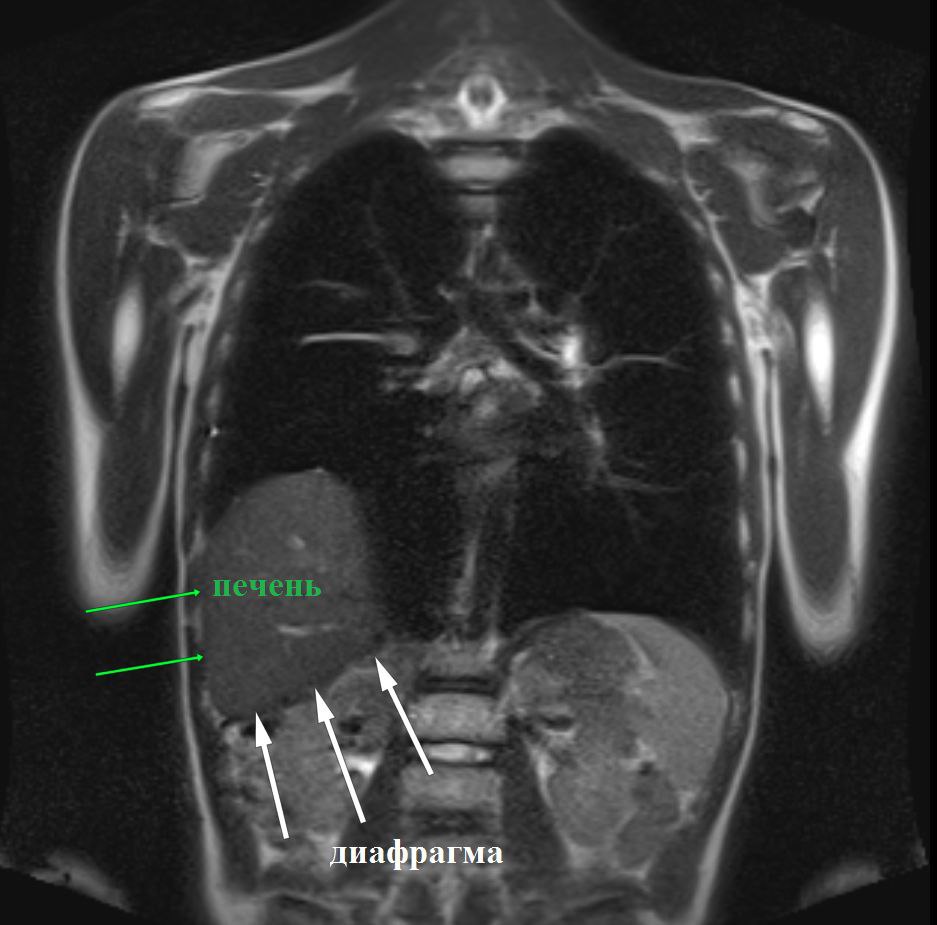

Диафрагмальную грыжу у мальчика обнаружили случайно, когда у ребенка развилась пневмония, и рентгеновское обследование выявило аномалию. Это редкий случай: как правило, такие грыжи диагностируются в младенческом возрасте, но в данном случае патология оставалась незамеченной целых 13 лет.